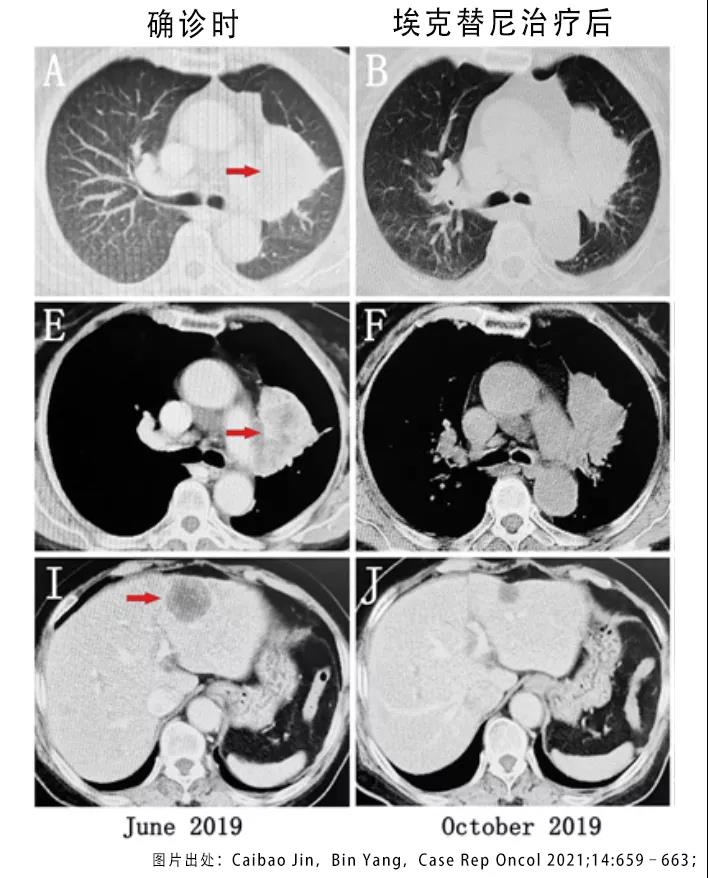

患者开始使用第一代EGFR基因的靶向药物埃克替尼进行治疗,一个月以后进行的复查表明原发病灶没变化,但肝脏、肾上腺和纵膈淋巴结的转移灶明显缩小。临床医生评估为转移灶部分应答,原始病灶是稳定状态。

图1 病情确诊和靶向药物治疗后的CT检查结果 图1 病情确诊和靶向药物治疗后的CT检查结果